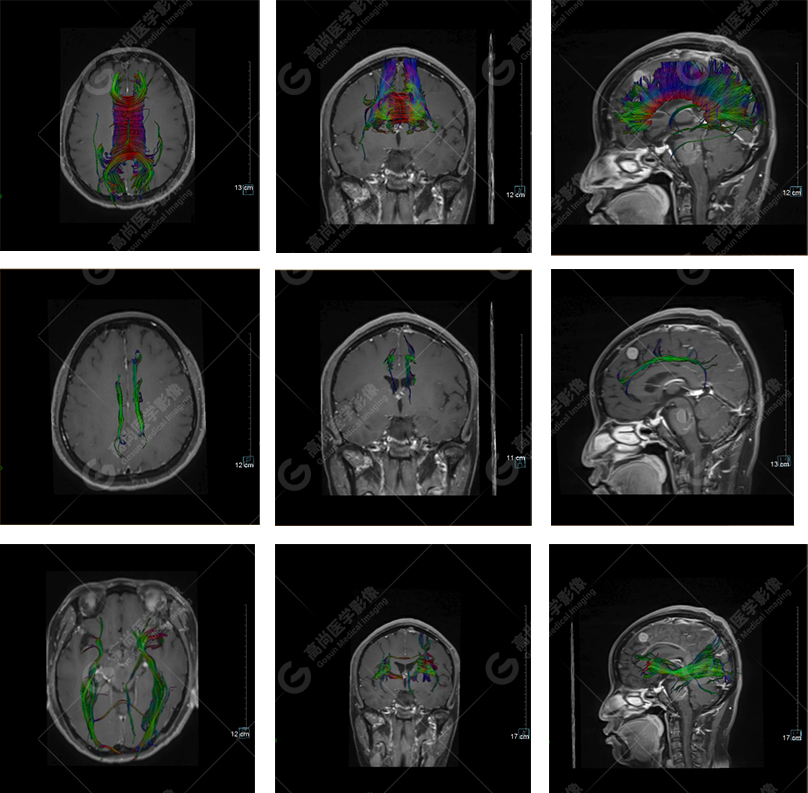

以上是常規(guī)顱腦MRI對(duì)病灶作出的診斷,可以看出,患者橋腦及大腦鐮各有一病灶,那么兩個(gè)病灶是否對(duì)顱腦神經(jīng)纖維束走行都有影像呢,下面是橋腦病變附近的神經(jīng)纖維束成像——皮質(zhì)脊髓束:

DTI成像示皮質(zhì)脊髓束橋腦段受壓向外側(cè)移位。圖像能清楚的顯示神經(jīng)纖維束與病灶的關(guān)系,是一種推壓移位的表現(xiàn)。

下面是其他神經(jīng)纖維束成像:

胼胝體束、雙側(cè)扣帶束及額枕束形態(tài)可,纖維束未見明顯破壞,未見明顯稀疏減少。大腦鐮旁的病灶對(duì)神經(jīng)纖維束走行并沒有什么影響。